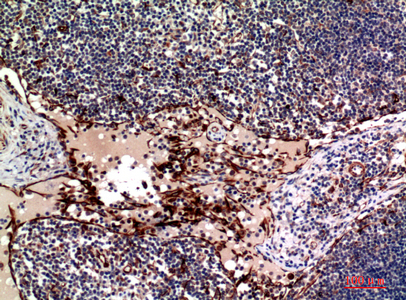

Immunohistochemistry analysis of paraffin-embedded Human lymph using OX40L antibody.High-pressure and temperature Sodium Citrate pH 6.0 was used for antigen retrieval. |